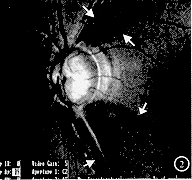

由具有相当经验的研究者判断视网膜神经纤维层状况,分为4种类型:(1)正常视网膜神经纤维层,表现为与视乳头相连的细条索放射状结构(图1)。(2)局灶性缺损或楔形缺损,表现为与视乳头相连的楔形的反光减弱区(图2)。(3)弥漫型缺损,表现为大片的神经纤维层的变薄、发暗,视网膜下小血管清晰可辨,尤其是视乳头上、下血管弓区(图3)。(4)裂隙状缺损,表现为与视乳头相连的裂隙状的暗区(图4)。

图1 正常视网膜神经纤维层